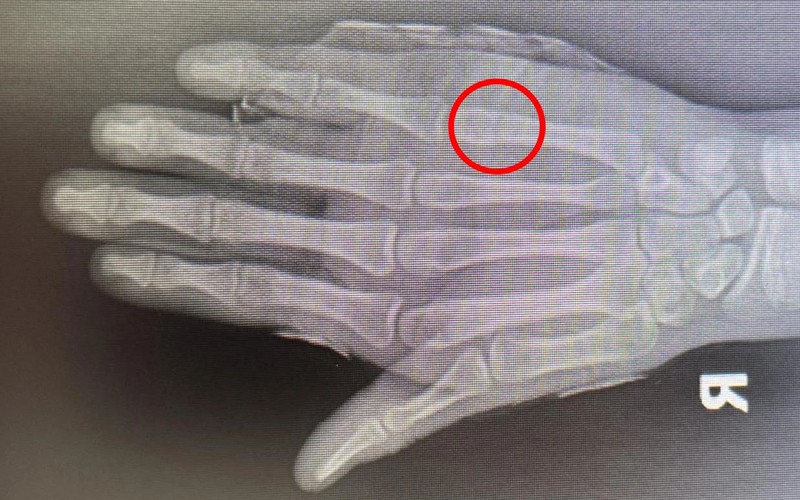

患者小徐今年16岁,因在学校不慎撞伤导致右手肿痛难忍来院就诊,穆中杰教授与科室医生认真研判病情,考虑患者为掌骨骨折可能,经过检查显示右手第5掌骨颈骨折,又称“拳击手骨折”,是临床上比较常见的手部骨折。

同患者及其家属进行沟通,决定行手法复位+杉树皮夹板固定,同时使用金黄散外用消肿止痛治疗,复位后骨折基本达解剖复位,患者及家属十分满意。

遂再次就诊于我院,经穆教授手法复位后,检查显示骨折复位良好。